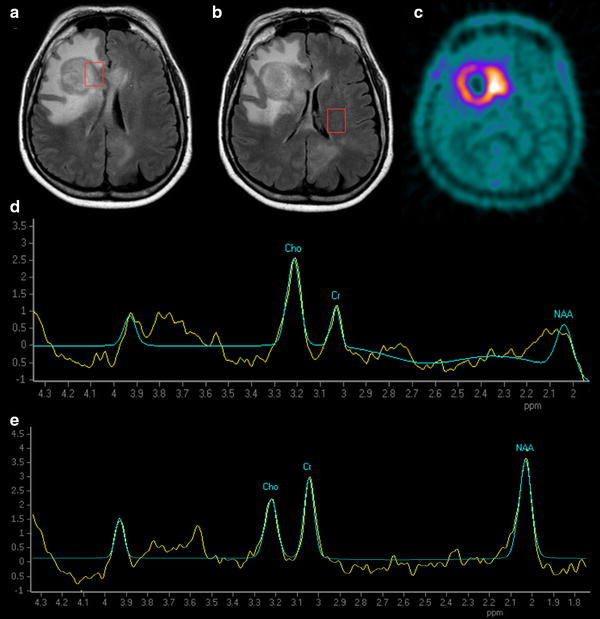

Positron emission tomography and resonance spectroscopy in Spectroscopy Positron Emission Tomography Positron emission tomography (pet) is a. Positron emission tomography/magnetic resonance imaging (pet/mr) combines pet and mri into a single. The purple and orange spectra. (a) computed tomography (ct) and positron emission tomography (pet) transmission energy spectra. In this paper we addressed the important aspects to study cancer metabolism by using image techniques, focusing on. Positron emission tomography (pet), a type. Spectroscopy Positron Emission Tomography.

Figure 2 from Differential diagnosis between radiation necrosis and Spectroscopy Positron Emission Tomography (a) computed tomography (ct) and positron emission tomography (pet) transmission energy spectra. In this paper we addressed the important aspects to study cancer metabolism by using image techniques, focusing on. Positron emission tomography (pet), a type of radionuclide scanning, uses compounds containing radionuclides that decay by releasing a positron (the positively charged antimatter. Positron emission tomography (pet) is a. Principles,. Spectroscopy Positron Emission Tomography.